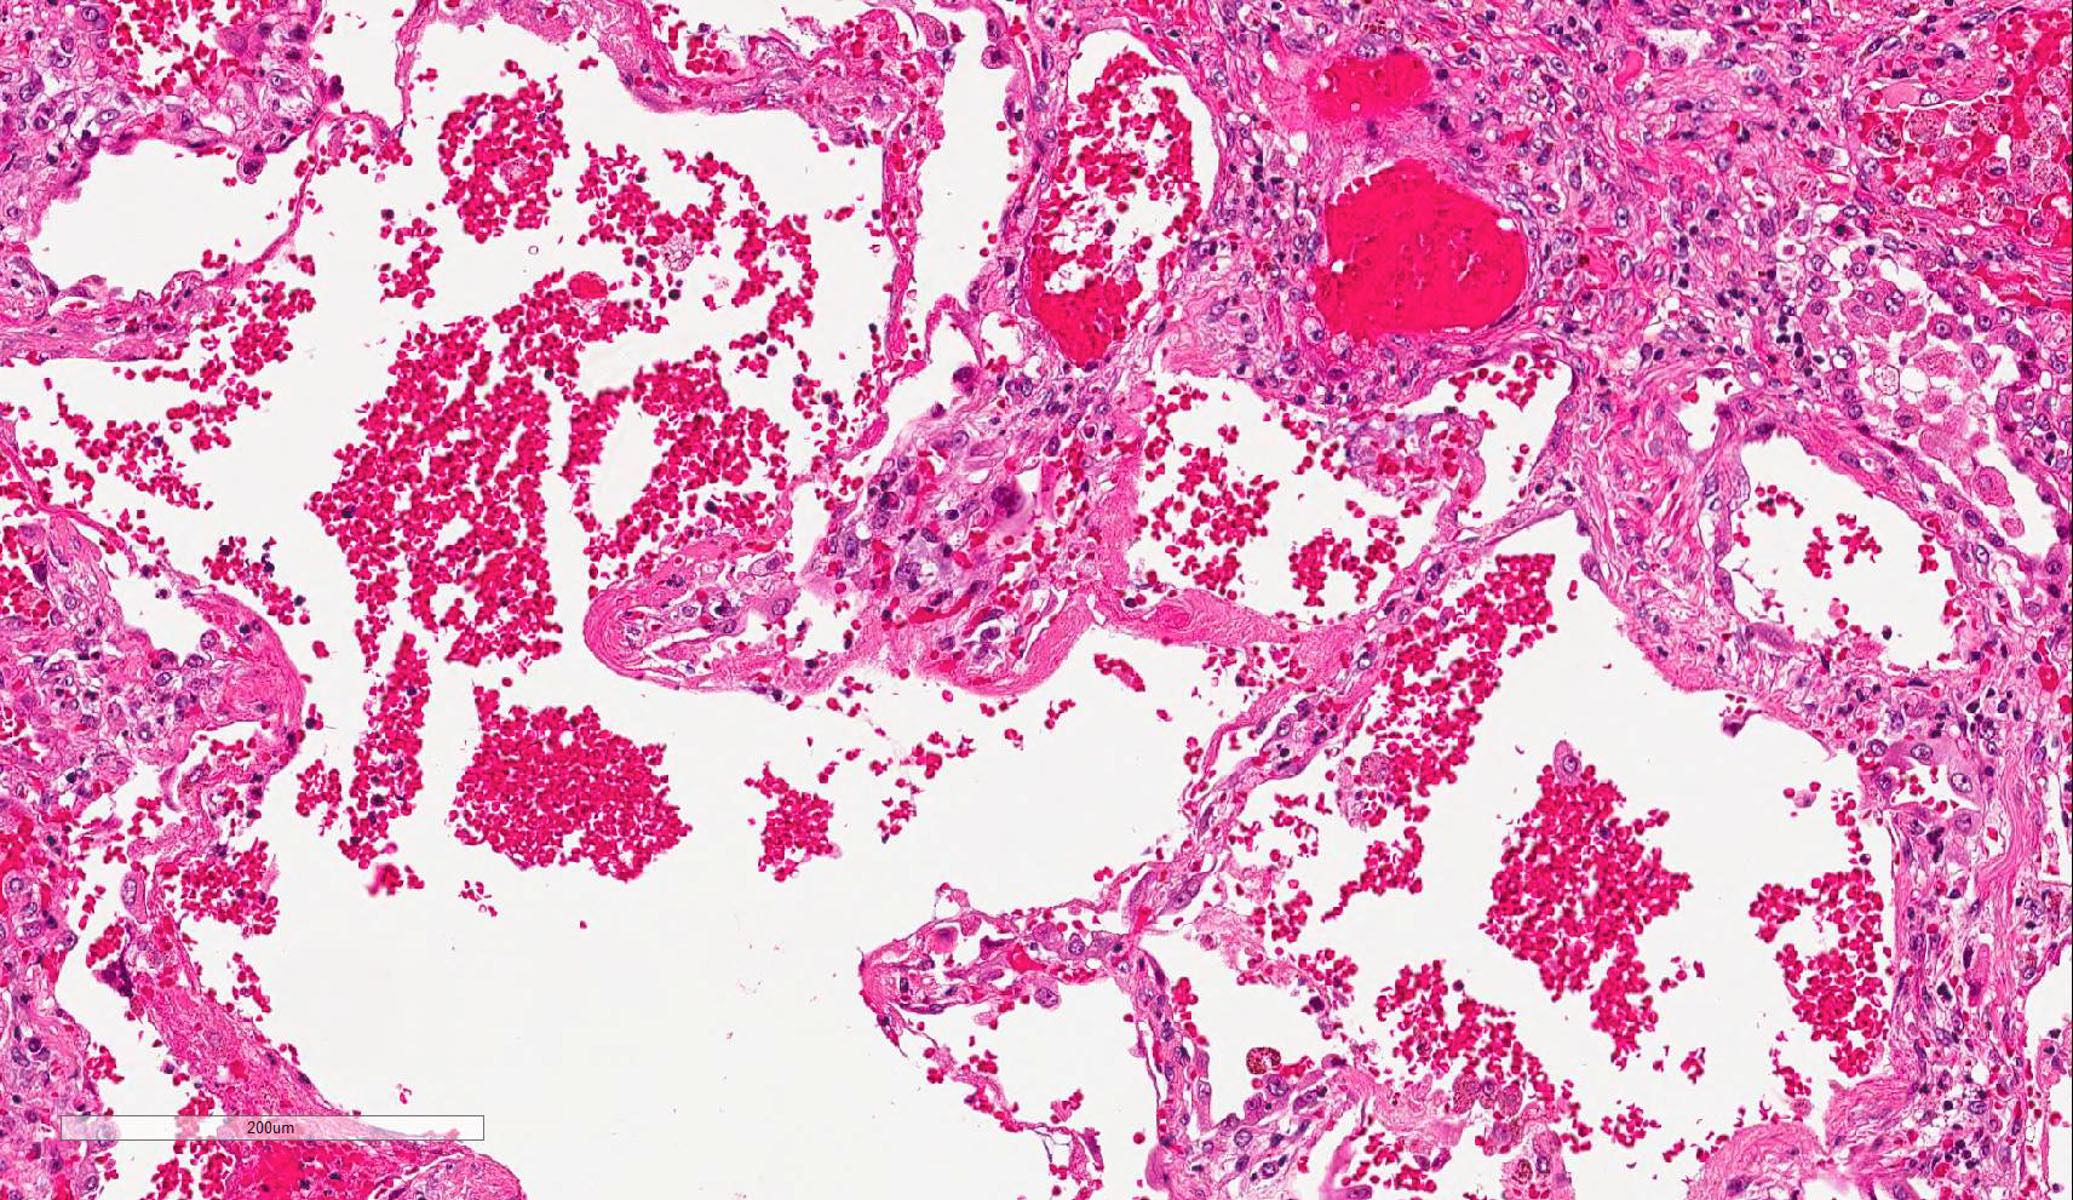

Microscopic (histologic) description

- Histopathology of DAD progresses from exudative (acute) phase through proliferative / organizing (subacute) phase to chronic fibrotic phase roughly corresponding to the period of ARDS (Am J Pathol 1976;85:209, Arch Pathol Lab Med 2010;134:719, Clin Chest Med 2000;21:435, N Engl J Med 2000;342:1334)

- Exudative (acute) phase

- Vascular change

- Necrosis of endothelial cells

- Neutrophil aggregation

- Microthromboemboli

- Hemorrhage

- Alveolar change

Microscopic (histologic) images

Contributed by Akira Yoshikawa, M.D. and Yale Rosen, M.D.